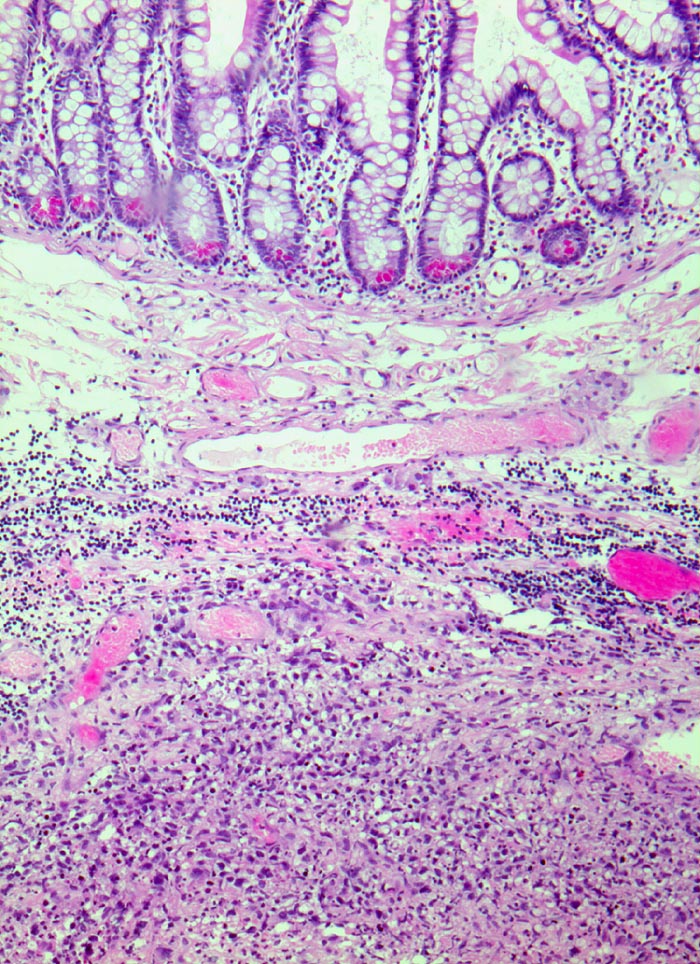

extranodales diffuses grosszelliges B-Zell Lymphom (WHO)

Ileum

Grosszelliges Lymphominfiltrat in der Submukosa.

Immunhistochemie: CD20 positiv, CD3 und CD30 negativ, CD117 negativ

Akute Peritonitis bei Darmperforation

Histologie

50